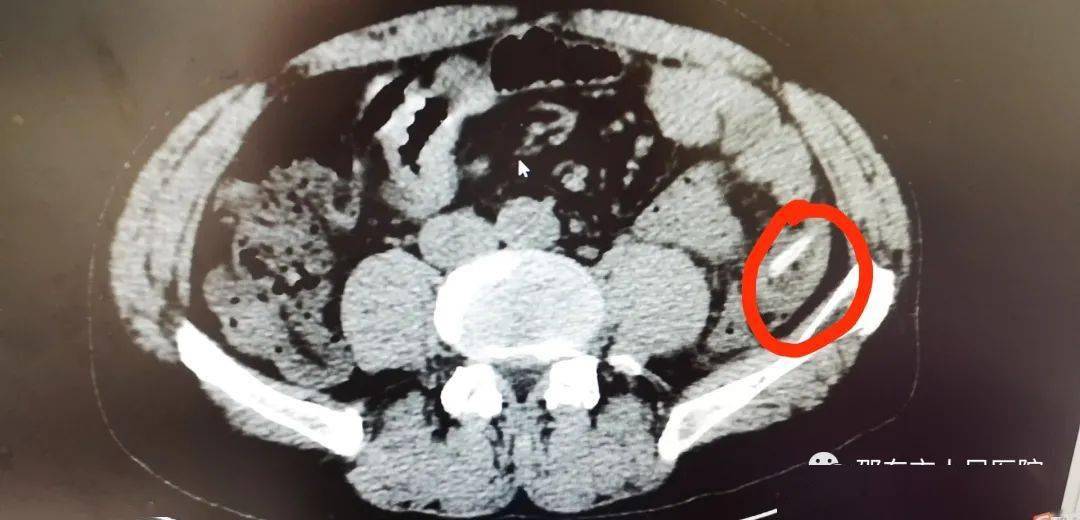

为啥医生总让您完善检查吃鱼3天后3cm鱼刺让他肠穿孔

图片尺寸942x861